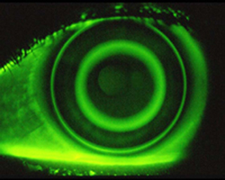

オルソケラトロジーは、夜間寝ている間にハードコンタクトレンズに似た材質のコンタクトレンズを装用することで、角膜(黒目)を型押しして平坦化させ、近視を矯正する治療法です。